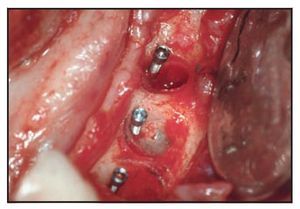

Figura 2a El paciente presentó una pérdida ósea evidente alrededor de tres implantes cilíndricos en el maxilar inferior izquierdo.

Figura 2b El defecto óseo asociado a los implantes fallidos tras la degranulación pero antes de la retirada del implante.

Figura 2c Colocación de los minitornillos tras la retirada de los implantes.

Figura 2d (izquierda) Material de injerto colocado alrededor de los minitornillos.

Figura 2e (derecha) Colocación de la membrana reforzada con titanio sobre la cresta injertada y los minitornillos.

Figuras 2f y 2g Aspecto clínico y radiográfico de la cresta ósea 15 meses después del injerto pero antes de la retirada de los minitornillos y la colocación de los implantes. La retirada de la membrana se realizó 2 meses después del injerto.